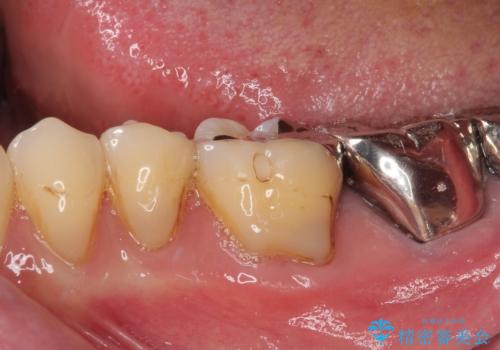

- 奥歯で食事がとれないくらいに痛むとのことで来院された患者です。

診察の結果、既に根管治療をされている第二大臼歯の根尖部に大きな病変があり、それが痛みの原因であるため、根管治療が必要と判断されました。

速やかに根管治療を行い、痛みの消退を確認の後、オールセラミッククラウンにて補綴治療を行うこととしました。